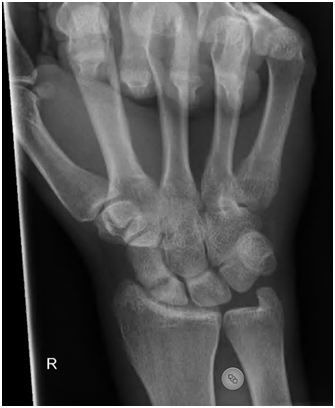

Scaphoid fractures are the commonest carpal fracture yet a potentially serious injury resulting in considerable disability (non-union / arthritis) if inadequately treated. Scaphoid fractures are commonly missed partly because the clinical signs are often unimpressive and 25 % of initial XRs will fail to show a scaphoid fracture when there is one. The scaphoid has a poor blood supply which is why even in fit and healthy patients it sometimes fails to heal. Smoking is considered a poor prognostic factor for scaphoid union.

If a scaphoid fracture is suspected an MRI scan may be necessary (advised by NICE guidelines) to confirm if X-rays are not 100% diagnostic.

The treatment of a scaphoid fracture depends on the personality of the fracture: displaced, undisplaced, proximal pole vs distal pole vs waist fracture. Your surgeon will discuss the different types with you.

A completely undisplaced scaphoid fracture (difficult to see on XR) can be treated with good success in a plaster. This plaster does not need to include the thumb but the average time in plaster is between 8-12 weeks.